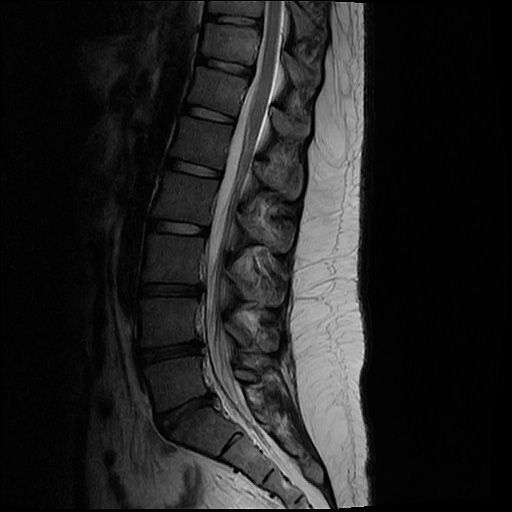

20살 허리디스크 심각한가요?

목디스크 허리디스크 둘다 가지고 있는데 목 몇번이랑 허리 몇번이 터졌고 어느정도 상태인건가요??

올리신 사진들만으로 정확한 디스크 평가가 가능하지는 않습니다. 하지만 사진의 소견들만 보았을 때에는 심하지는 않습니다.

MRI 4컷으로는 디스크 탈출의 정도를 충분히 확인이 불가능합니다.

현재 주어진 사진에서는 허리 디스크는 확인이 가능한 상태이며 그 중등도는 명확히 확인이 어렵습니다.

현재 mri에서는 디스크가 돌출된 부분이 확인됩니다. 디스크가 돌출되었다고 반드시 수술적 치료를 하는 것은 아닙니다. 디스크는 재흡수 되는 경우도 많기에 보존적 치료를 하면서 경과를 보실수 있습니다. 다만 증상이 너무 심하거나 보존적 치료에도 호전이 되지 않는다면 시술이나 수술적 치료를 고려할수 있습니다.